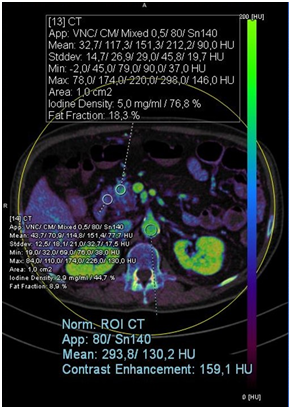

Pancreas head injury was also visualized on PET-CT and confirmed as squamous cell carcinoma with biopsy. In the iodine map, we can observe with greater definition the lesion with the attenuation of the amount of iodine, which is even more evident in monoenergetic 40 keV and we visualize it texturally by cinematic rendering, as showed in Figure 1. Quantitative analysis revealed increased Iodine enhancement (carcinoma: 5.0mg/ml; 76.8% versus normal tissue: 2.9 mg/ml; 44.7%), as well as Fat Fraction (carcinoma: 18.3% versus normal tissue: 8.9%) and greater standard deviation, what may represent greater heterogeneity of analyzed tissue when compared to the normal tissue (Figure 2).

Figure 1 Mixed image, axial slices of the upper abdomen, demonstrating squamous cells carcinoma lesion in the head of the pancreas, where 1 = computed tomography; 2 = cinematic rendering; 3 = iodine map; 4 = 40 keV monoenergetic; 5 = PET-CT to compare.